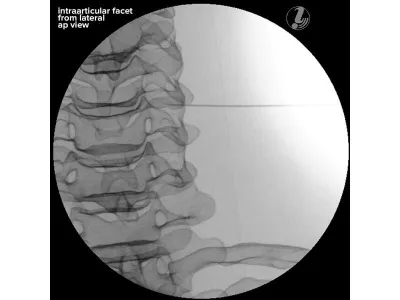

- Инъекция в фасеточный сустав шейного позвонка

Тренажер для отработки инъекций обеспечивает реалистичные тактильные ощущения при вводе инъекции, а также анатомически точную костную структуру с легкой локализацией.